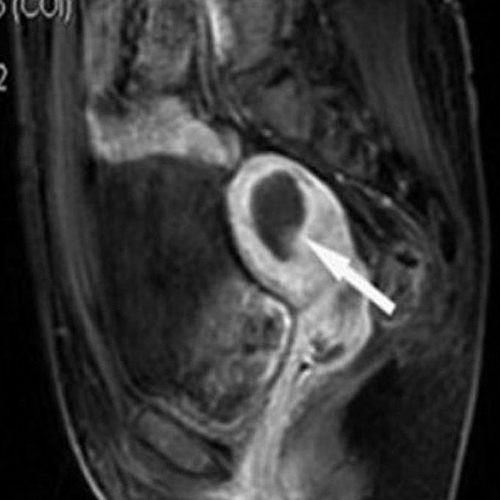

Зөв дүгнэлт гаргахын тулд MRI зэрэг нарийн шинжилгээ хийлгэх шаардлагатай.

9см том миома оношлогдсон

Тринитид ирж

Өндөр давтамжит эмчилгээ хийсэн

Эмчилгээс хойш 10 сарын дараа

2см болж хэмжээ 77% багассан